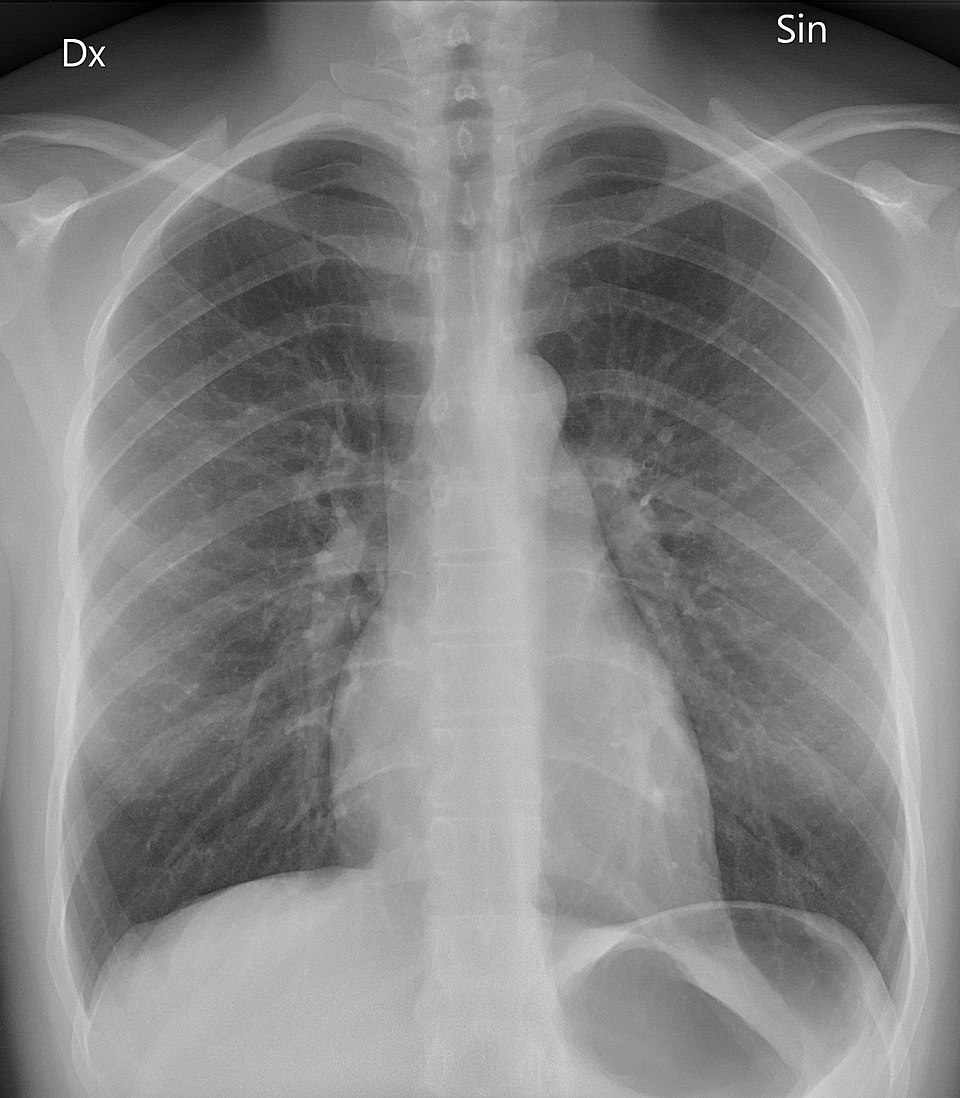

Chest X-ray

Chest X-rays reveal hidden battles within the body’s most vital cavity

What is a major limitation of chest X-rays compared to advanced imaging techniques like CT scans?

They provide less detailed information, requiring further tests for precise diagnosis.